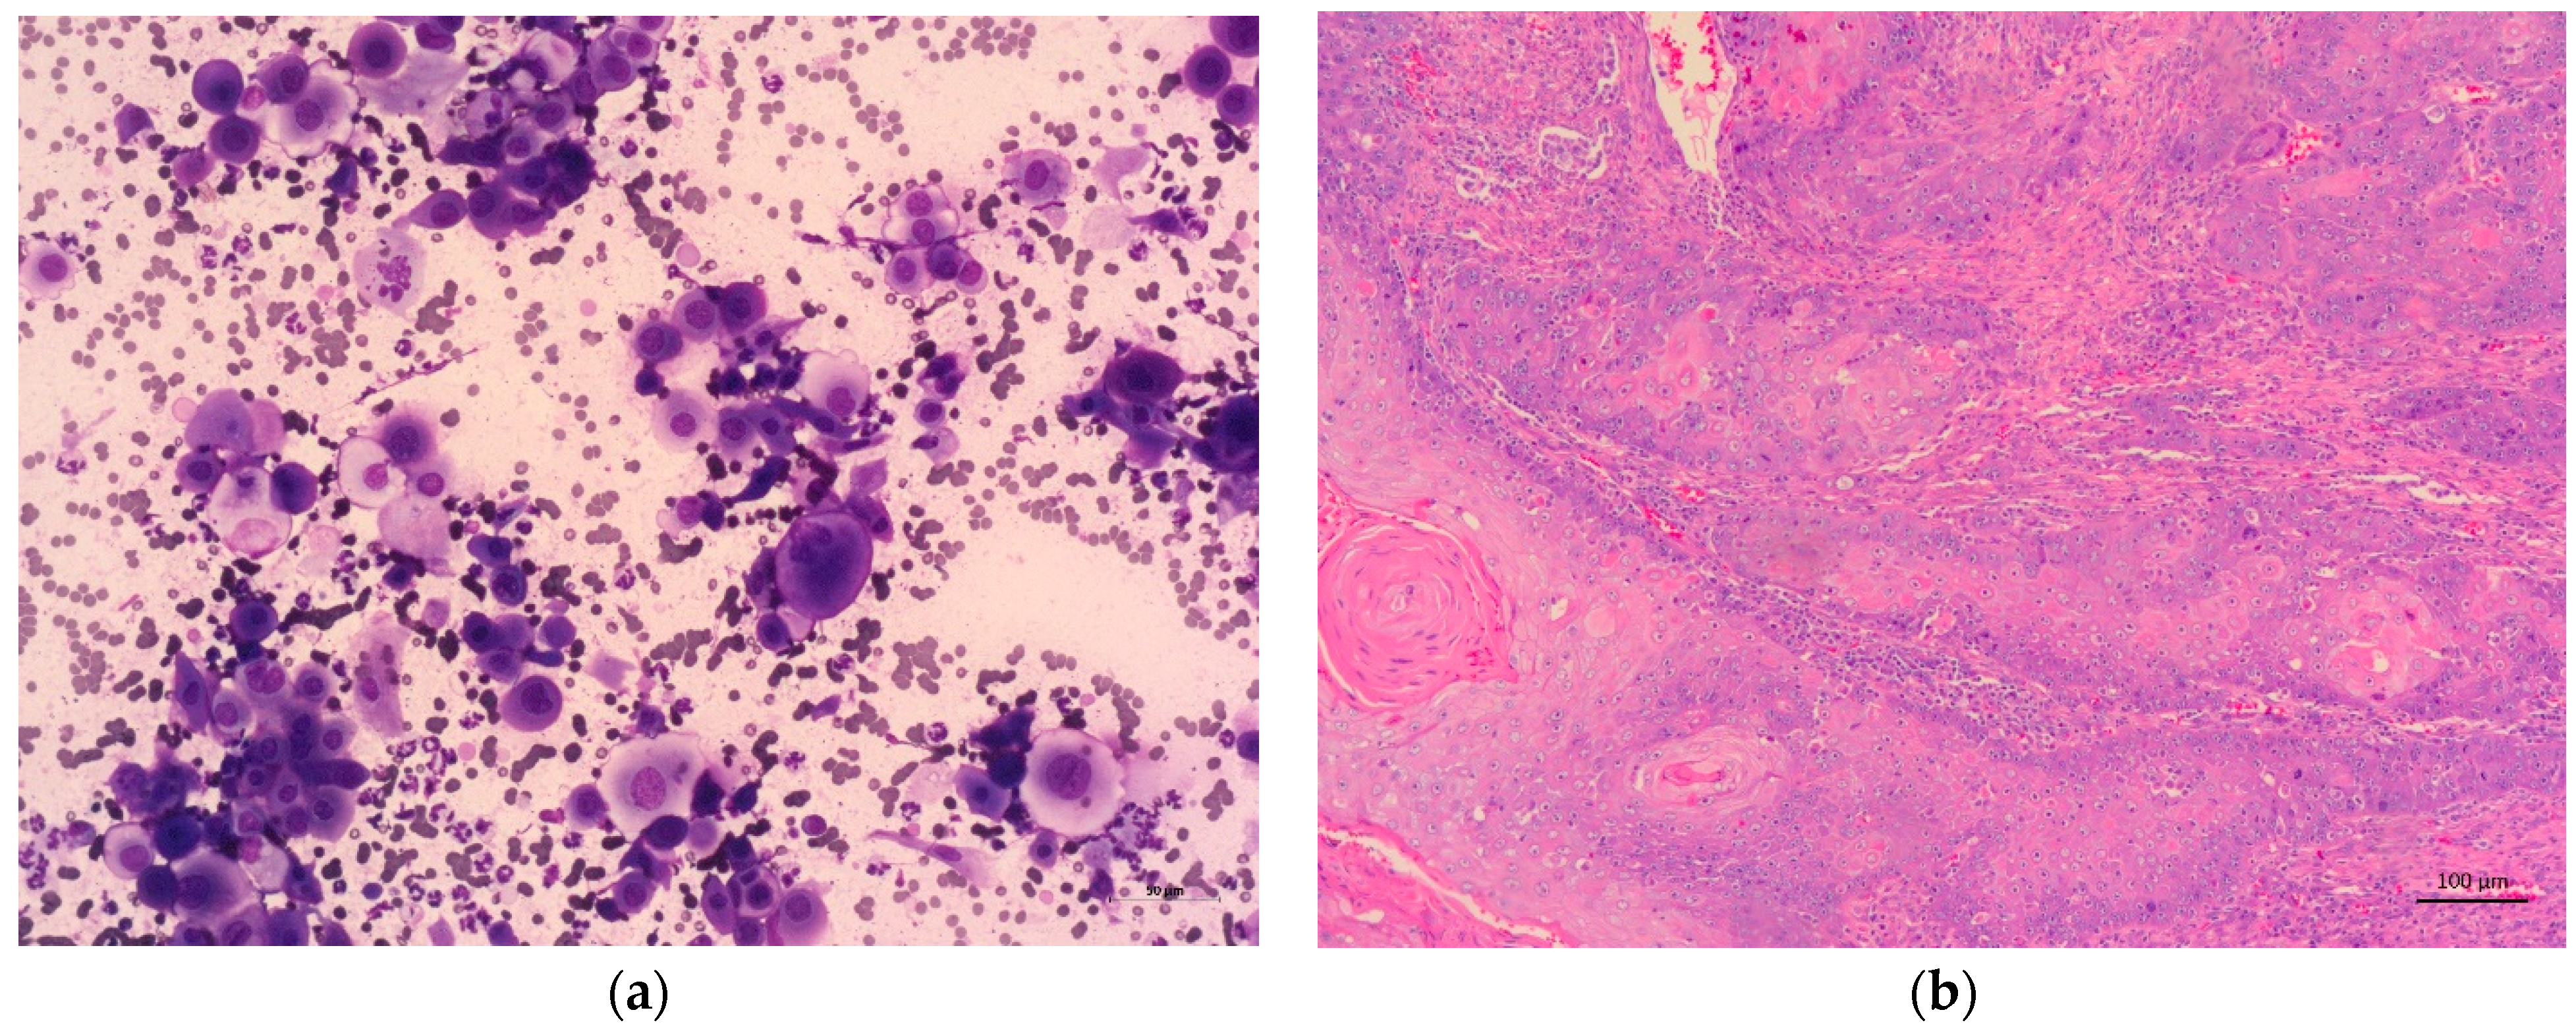

3.3. Oral Lesions—Diagnosis